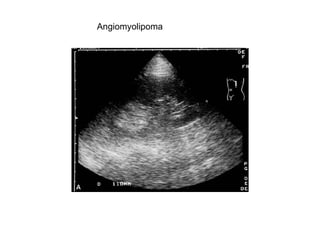

Angiomyolipoma

Angiomyolipoma confirmed by ct

Small angiomyolipoma. Small angiomyolipmas are often of an even,high echo density